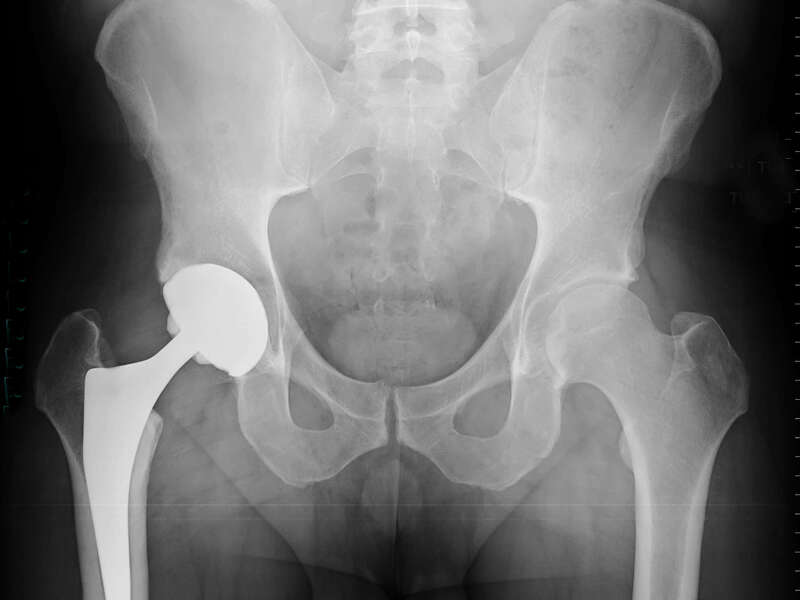

Les composants d’une Prothèse Totale de Hanche

Cette intervention consiste à remplacer l’articulation de la hanche par des composants artificiels qui reproduisent l’anatomie initiale de la hanche. Le type d’implant doit être adapté à chaque patient, en ce qui concerne sa forme, sa taille, la nature des matériaux entrant dans sa composition, son revêtement extérieur et la technique chirurgicale à employer.

Généralement une prothèse de hanche se divise en deux parties : une tige qui se place dans le fémur et une cupule en polyéthylène ou en céramique entourée d’une hémisphère métallique placée dans le cotyle. Les composants peuvent être fixés avec ou sans ciment chirurgical.

La tige que nous utilisons est une tige en titane non allié (norme ISO 5832-2) avec un revêtement en hydroxyapatite (norme ISO 13779-2) pour les tiges non cimentées.

La Cupule acétabulaire est en acier inoxydable (norme ISO 5832-9) avec un revêtement en poudre d’hydroxyapatite (norme ASTM 1185), et un insert en polyéthylène (norme ASTM F648).